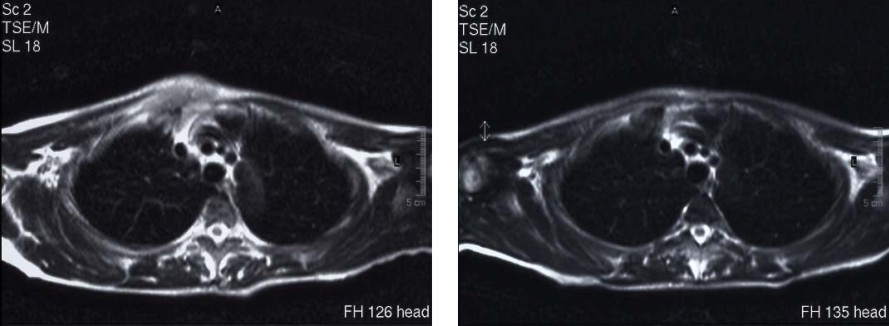

病例4 乳腺癌 stage IIIA

A 治疗前DSA示乳腺病灶 B 微血管介入后立即造影瘤染色消失

C 治疗前DSA D 治疗后3个月见病灶消失